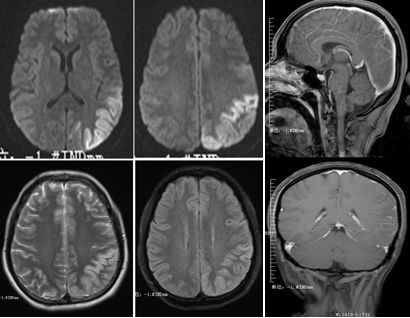

患者,女,27岁。发作性四肢抽搐20余天,精神行为异常10天入院。查体:颈抵抗(+++)。

答案:抗NMDA受体脑炎

这个患者的影像很有特点,皮层花边征,好多老师首先考虑到MELAS,但是患者颈部抵抗、左侧柔脑膜有强化等不好解释。影像表现为皮层花边征的同影异病有MELAS、自身免疫性脑炎、CJD等,一般来说,自身免疫性脑炎相对MELAS局限。患者青年女性,癫痫发作,精神行为异常应想到抗NMDA受体脑炎。抗NMDA受体脑炎儿童青年多见,女性多于男性。急性起病,可有发热,头痛等前驱症状。主要临床表现为精神行为异常,癫痫发作,近记忆力下降,言语障碍,运动障碍,不自主运动,意识水平下降,甚至昏迷等。头MRI可出现散在的皮层、皮层下点片状FLAIR及T2高信号,边缘系统病灶。